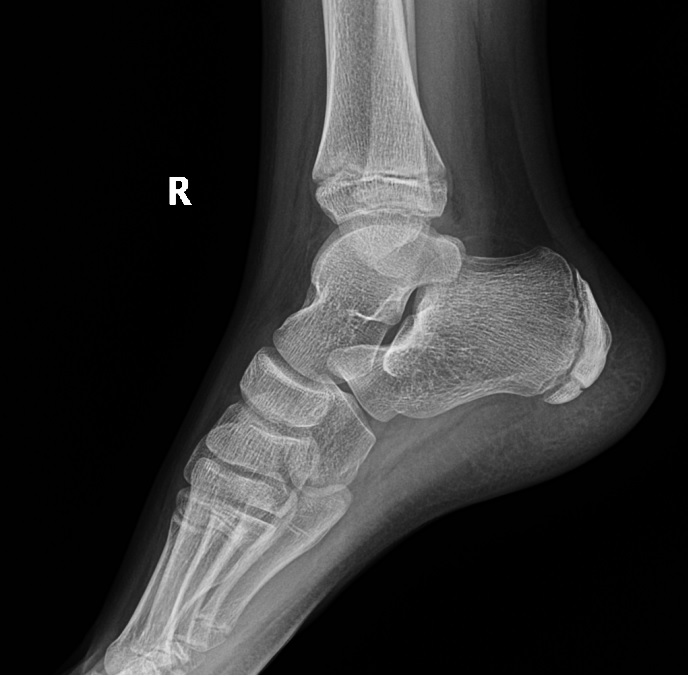

Заболевание проходит через несколько последовательных стадий, которые хорошо видны на рентгеновских снимках. Понимание стадии помогает врачу выбрать наиболее эффективную тактику лечения.

- Рентгенография. Это основной и наиболее доступный метод диагностики остеохондропатии. Снимки стопы в двух проекциях (прямой и боковой) позволяют увидеть характерные изменения в головке плюсневой кости, соответствующие определенной стадии заболевания.